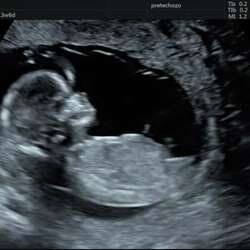

Dankjewel voor het delen van je verhaal, dat stelt echt enorm gerust! Weet je nog hoeveel mm de nekplooi was? Hier zag de verloskundige het somber in en zei ze letterlijk 'ik zie het niet gauw goedkomen met zulke grote metingen (8mm)'. Ben benieuwd wat ze in het erasmus gaan zeggen dan inderdaad. Maar je verhaal en gedeelde topic doet me goed! Dankjewel❤

Herkenbaar verhaal bij ons was alleen vocht gezien bij het buikje. Nekplooi was 2.1 mm. Wij zijn 2x voor een echo geweest in het UMC waar bij de 2e echo geen vocht meer te zien was. En ook geen afwijkingen. Nu krijgen we bij 20 weken (over 5 weken) ook een echo in het UMC. Weet iemand of dit het gebruikelijk is, of zouden de dokters zich alsnog zorgen maken?